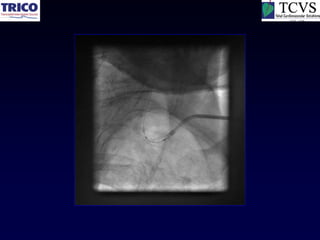

Catheter Knot

Reduction

Another example